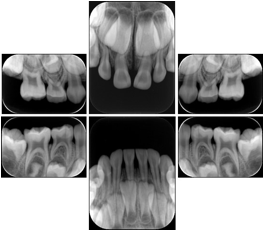

6 Standard Pedodontic + 2 bitewing layout A Dental Image Layout

DL-P002A

6 Standard Pedodontic + 2 bitewing layout B Dental Image Layout

DL-P002B

6 Standard Pedodontic + 2 bitewing layout C Dental Image Layout

DL-P002C

6 Standard Pedodontic + 2 bitewing layout D Dental Image Layout

DL-P002D

6 Standard + 4 Bitewing C Dental Image Layout

DL-P002E